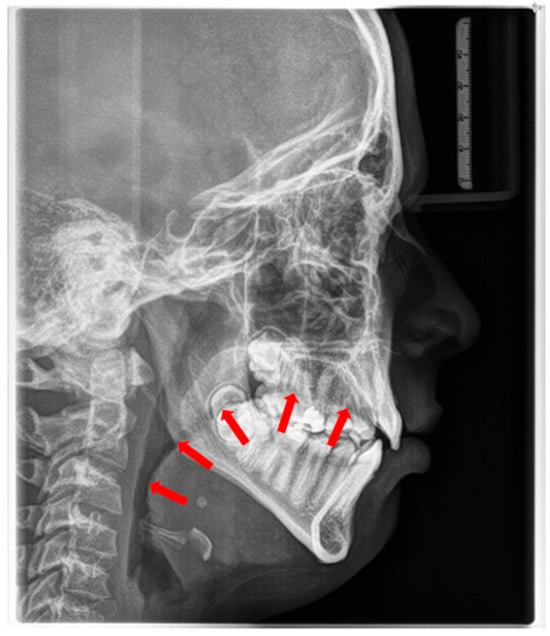

The consequences of these anatomical alterations result in a reduced size of the bony nasopharynx and a hyperdivergent facial pattern, characterized by increased anterior facial height. A bimaxillary retrognathic pattern, more pronounced in the mandible than the maxilla, and a decreased facial depth further contribute to a narrowed posterior airway space [83]. Together, these structural changes significantly reduce upper airway volume, thereby predisposing affected individuals to OSA (Figure 3).

These patients often exhibit “adenoid facies” characteristics and present with dark circles around the eyes, flattened cheekbones, dry lips, an open-mouth posture, a lowered mandibular posture, a low tongue position, labial incompetence, underdeveloped nasal bones, pronounced nasolabial furrows, which collectively complete the typical appearance [57,61,69,70,71]. They often present a convex profile due to a retrognathic mandible (Figure 4) and an increased mandibular angle. The lower facial third is frequently longer than the average (long-face, dolichofacial morphology) [69] (Table 2). Additionally, they exhibit an altered head position resulting from hyperextension of the cervical spine and an overall reduction in orofacial muscle tonicity.

Lateral cephalometry allows for systematic assessment of craniofacial structures, including both hard and soft tissues. Furthermore, it enables the evaluation of the sagittal dimension of the posterior airway space (PAS) and can therefore serve as a screening tool [101,102]. This diagnostic tool is reproducible, affordable, easily accessible in an orthodontic office, involves minimal radiation exposure, and is non-invasive [2] (Figure 6). The cephalometric radiographs are taken in an upright and natural head position, where the eyes focus ahead with a horizontal visual axis parallel to the floor (Frankfort horizontal plane). The occlusion should be the habitual bite (not forced into maximum intercuspation) and the lips in gentle contact (not forcefully closed).

Nevertheless, it is essential to note that the soft tissues in the upper airway behave differently when a person is asleep, in a supine position, compared to an upright position [103,104,105,106]. Several studies attempted to establish a relation between airway dimensions and craniofacial structures in subjects with OSA through cephalometric assessment [107,108,109].